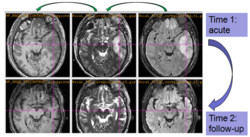

Experiments: Registration of longitudinal data

The NA-MIC DBP project on TBI analysis (UCLA partner) includes serial multi-modal MRI at acute phase and follow-up after six months. We test mutual-information-based linear registration of multi-modal MRI data within each time point and nonlinear registration (b-spline) of follow-up scans to obtain sets of images mapped into the same coordinate system.

Longitudinal co-registration of multi-modal MRI.

Segmented white matter and temporal lobe (yellow) at acute phase and after 6 month follow-up.